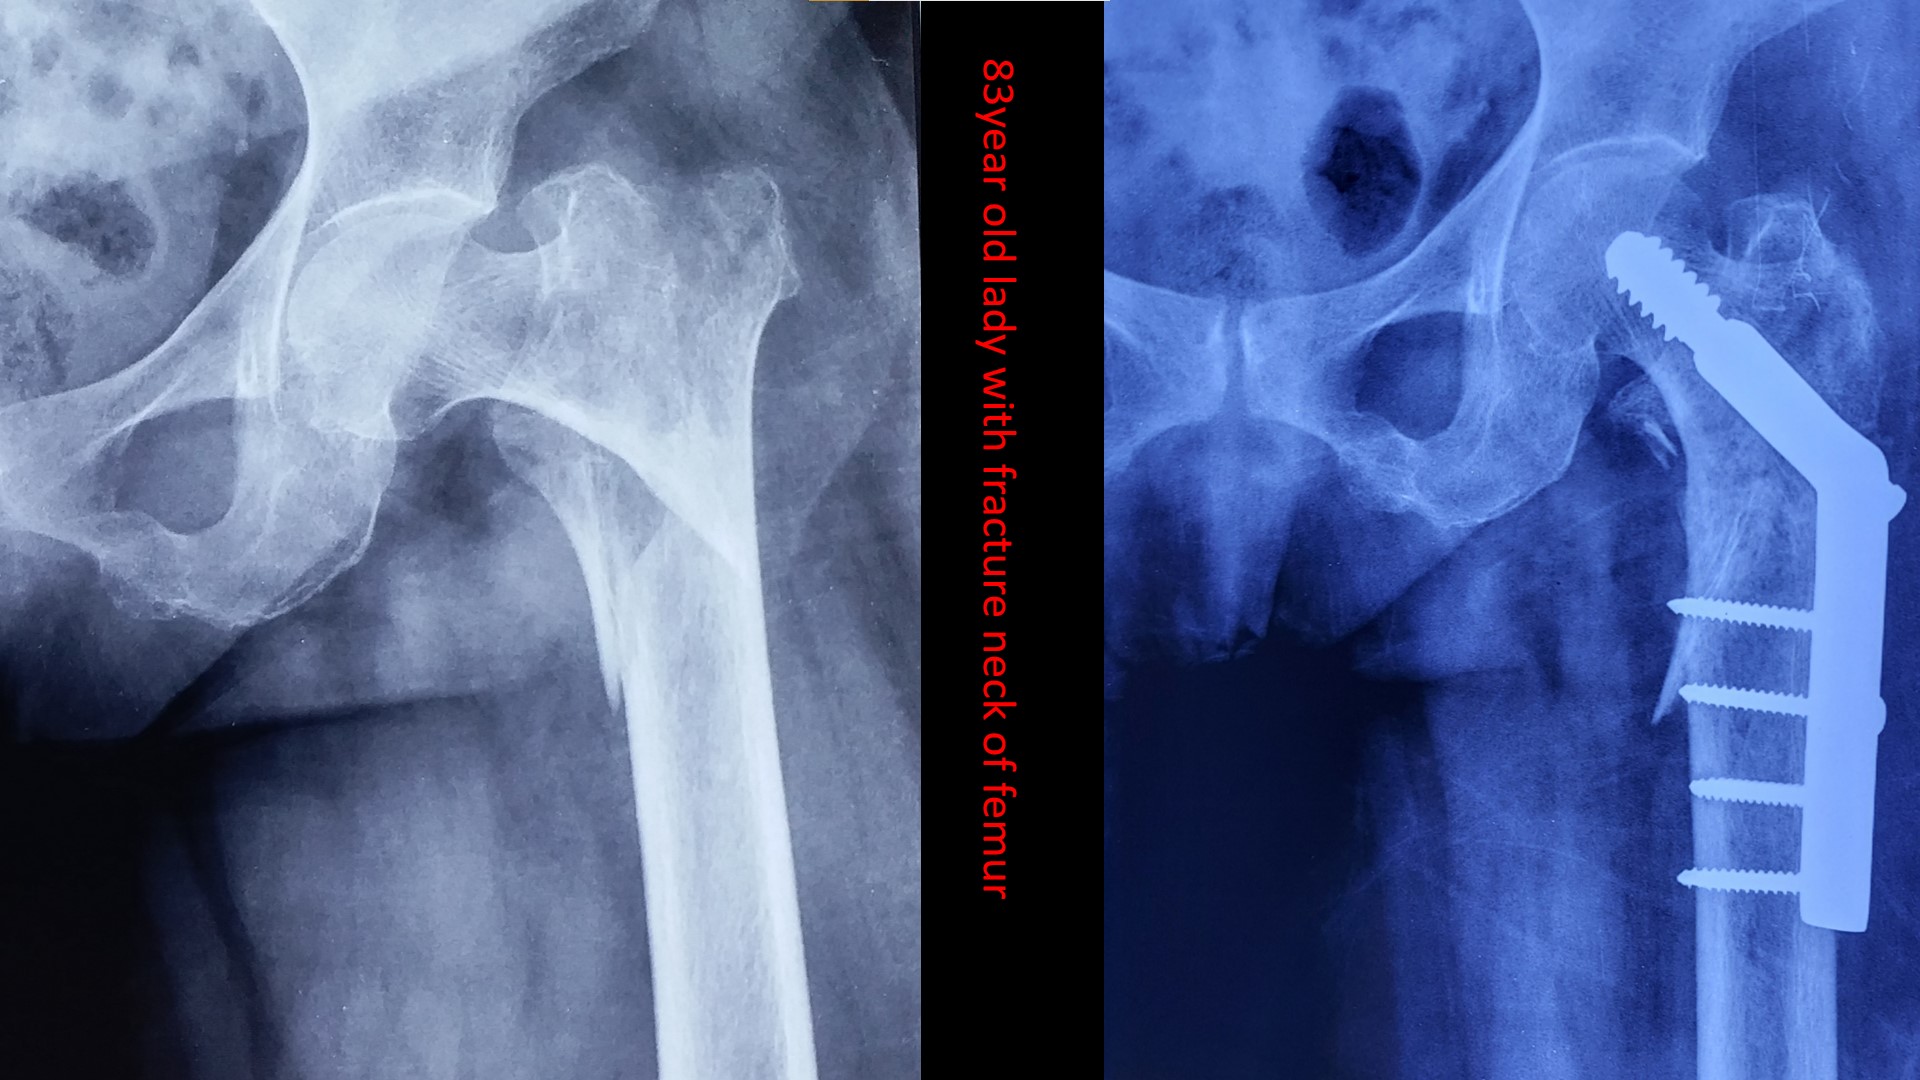

The care you deserve.

Please send us a message, or call us for an appointment. +919287283131,+9188166438,04662223131, 04662223785